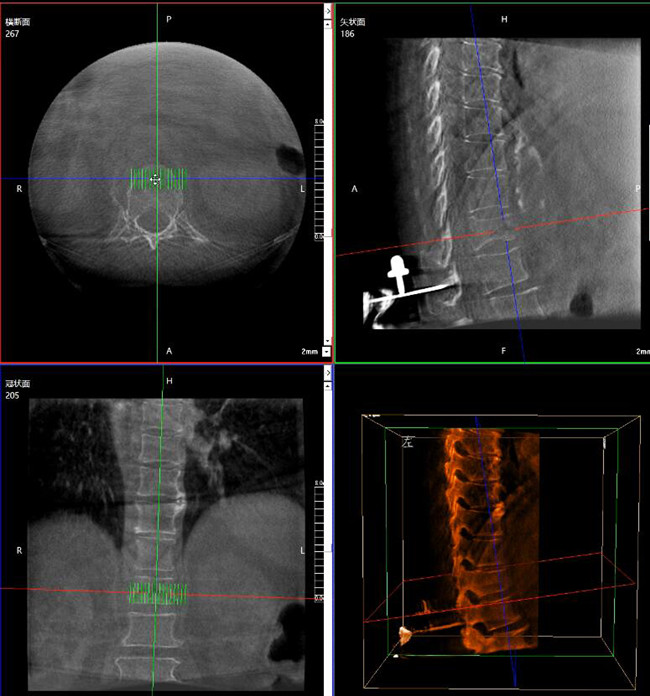

步驟一:C形臂三維重建+機器人手術規劃

使用普愛醫療三維C形臂對患者進行胸椎影像掃描及三維重建,圖像被同步傳輸到普愛醫療骨科機器人導航系統。

借助骨科機器人的規劃軟件進行術前手術路徑模擬規劃,找到穿刺位置和角度,操作機械臂快速完成手術入點的準確定位。

*術前規劃